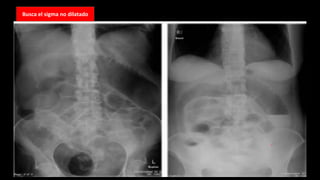

Busca el

sigma no

dilatado

Busca el sigma no dilatado

¿Qué esta dilatado?

Obstrucción de intestinogrueso Busca el sigma no dilatado

• 47.

Busca el sigmano dilatado